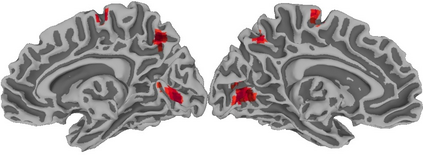

Functional Magnetic Resonance Imaging (fMRI) maps cerebral activation in response to stimuli but this activation is often difficult to detect, especially in low-signal contexts and single-subject studies. Accurate activation detection can be guided by the fact that very few voxels are, in reality, truly activated and that these voxels are spatially localized, but it is challenging to incorporate both these facts. We address these twin challenges to single-subject and low-signal fMRI by developing a computationally feasible and methodologically sound model-based approach, implemented in the R package MixfMRI, that bounds the a priori expected proportion of activated voxels while also incorporating spatial context. An added benefit of our methodology is the ability to distinguish voxels and regions having different intensities of activation. Our suggested approach is evaluated in realistic two- and three-dimensional simulation experiments as well as on multiple datasets. Finally, the value of our suggested approach in low-signal and single-subject fMRI studies is illustrated on a sports imagination experiment that is often used to detect awareness and improve treatment in patients in persistent vegetative state (PVS). Our ability to reliably distinguish activation in this experiment potentially opens the door to the adoption of fMRI as a clinical tool for the improved treatment and therapy of PVS survivors and other patients.